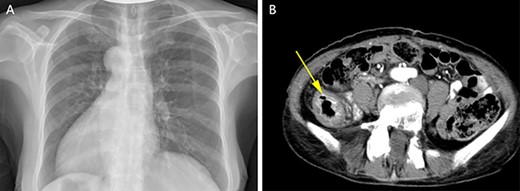

After sufficient preoperative preparation and discussion, we decided to perform open radical resection of colon cancer operation for the patient. During surgery, we found that the tumor was located in the lower part of the descending colon (in the right abdominal cavity), the size of the tumor was ~4.0 x 5.0 cm in diameter, the boundary between the tumor and the surrounding tissue was clear and the tumor invaded the whole intestinal wall. Moreover, the patient’s the left ovarian vessels were significantly thickened, especially the veins (Fig. 3A), and the inferior mesenteric vessels were absent (Fig. 3B). The operation time was 115 min and intraoperative blood loss was 33 ml. Histological examination of the resected specimens revealed a moderately differentiated carcinoma (Fig. 3C). On postoperative Day 1, the laboratory examination showed that white blood cell count was 13 600/mm3, and neutrophil cell count was 12 300/mm3. These results showed that the leukocytes and neutrophils were significantly increased, and antibiotics were applied to prevent the occurrence of infection in consideration of aseptic inflammatory reaction in the operation area and systemic stress reaction. There was no obvious abdominal pain, chills, fever and other discomfort in the patient after operation. The drainage tube outflow was a pale red liquid (~50 ml/day). The anal exhaust time was on postoperative Day 3 and the patient started a fluid diet. However, on postoperative Day 5, the peritoneal drainage volume had increased to ~500 ml/day and the liquid had become pale yellow, which was confirmed as lymphatic leakage by Sudan III staining (data not shown). Treatment with low-fat diet for 5 days, the drainage fluid of the patient was significantly decreased to ~10 ml/day and then the drainage tube was removed as B-ultrasonography examination showed almost no remaining liquid in the abdominal cavity. The final pathological report of the case showed a moderately differentiated carcinoma and stage T4aN0M0. The patient was discharged on postoperative Day 10 and followed up for 1 year without tumor recurrence or tumor metastasis. No special discomforts and complications were mentioned in the 1 year followed-up period (data not shown).

The left ovarian blood veins were significantly thickened (A, blue arrow), and the tumor was located in the descending colon (A, yellow arrow); the inferior mesenteric blood vessels were absent, the left colon blood vessels (B, blue arrow) and the left ureter (B, yellow arrow) were marked. Pathological examination showed a moderately differentiated adenocarcinoma (C).